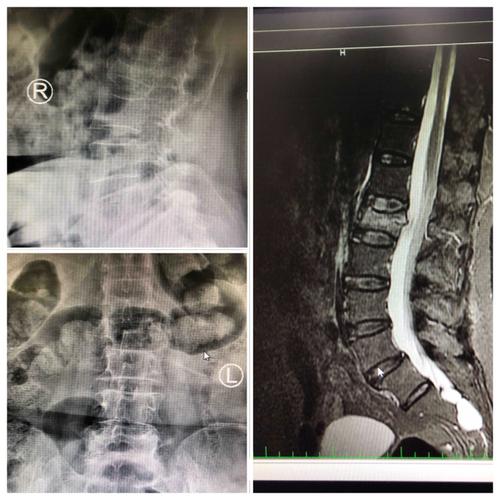

腰椎正侧位x光片:可见腰1椎体压缩性骨折 上终板塌陷,椎体前缘骨折块

腰椎压缩性骨折图片ct